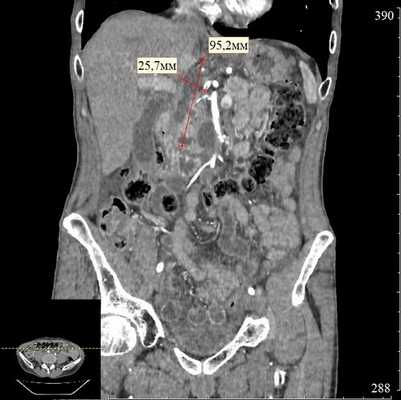

При эндосонографии (эндоУЗИ) в области головки поджелудочной железы визуализировано анэхогенное образование с четкими неровными контурами неправильной продольной формы, размерами 3,1х10 cм, прилежащее к воротной вене - постнекротическая киста с преимущественно внеорганным расположением (рис. 3).

Риски и особенности ситуации

К особенностям ситуации нужно отнести крупный размер и сложную конфигурацию кисты, ее преимущественно внеорганное расположение и близость воротной вены. Для того чтобы оценить пространственное соотношение кисты с прилежащими анатомическими структурами, а также определить наилучшее место для дренирования, была проведена 3D виртуальная компьютерная реконструкция (рис. 4).